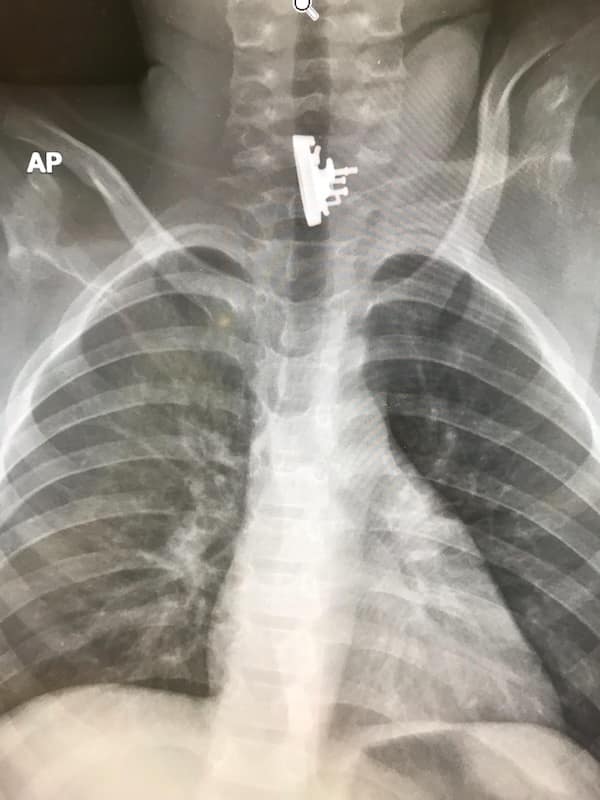

Weird xray photos

I used to think that nothing could surprise me anymore—until I stumbled upon some weird x-ray photos that made me reconsider my stance on human ingenuity (or lack thereof). Apparently, some people have a knack for getting objects lodged where they absolutely shouldn’t be. If you’ve ever wondered how not to use everyday items, these images might provide some unintended guidance.

This collection showcases 31 bizarre x-ray images that defy logic and anatomy textbooks alike. Each photo reveals unexpected objects making cameo appearances inside the human body, turning medical imaging into a gallery of the absurd. From common household items inexplicably found in unusual places to anomalies that would leave even seasoned doctors scratching their heads, these images offer a perplexing glimpse into the more “creative” side of medical emergencies. They highlight the intersection of curiosity, misadventure, and perhaps a dash of poor decision-making, all captured through the lens of radiology.